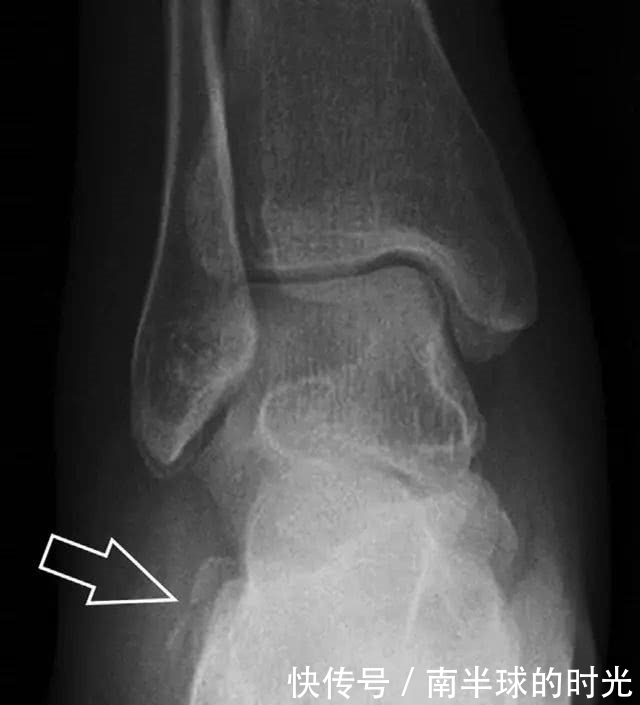

趾短伸肌跟骨撕脱性骨折

另一种重要的跟骨撕脱性骨折,于足内翻时发生在趾短伸肌的起点处。观察来自跟骨背外侧的、不同大小的骨折块,前后位 X 片最适合不过了(图 7)。

图 7 溜冰受伤的患者,趾短伸肌跟骨撕脱性骨折。正位片示 2 个骨折块(箭头)来源于跟骨前外侧、趾短伸肌的起点处。踝关节外侧远端是否存在软组织水肿是一个重点观察点